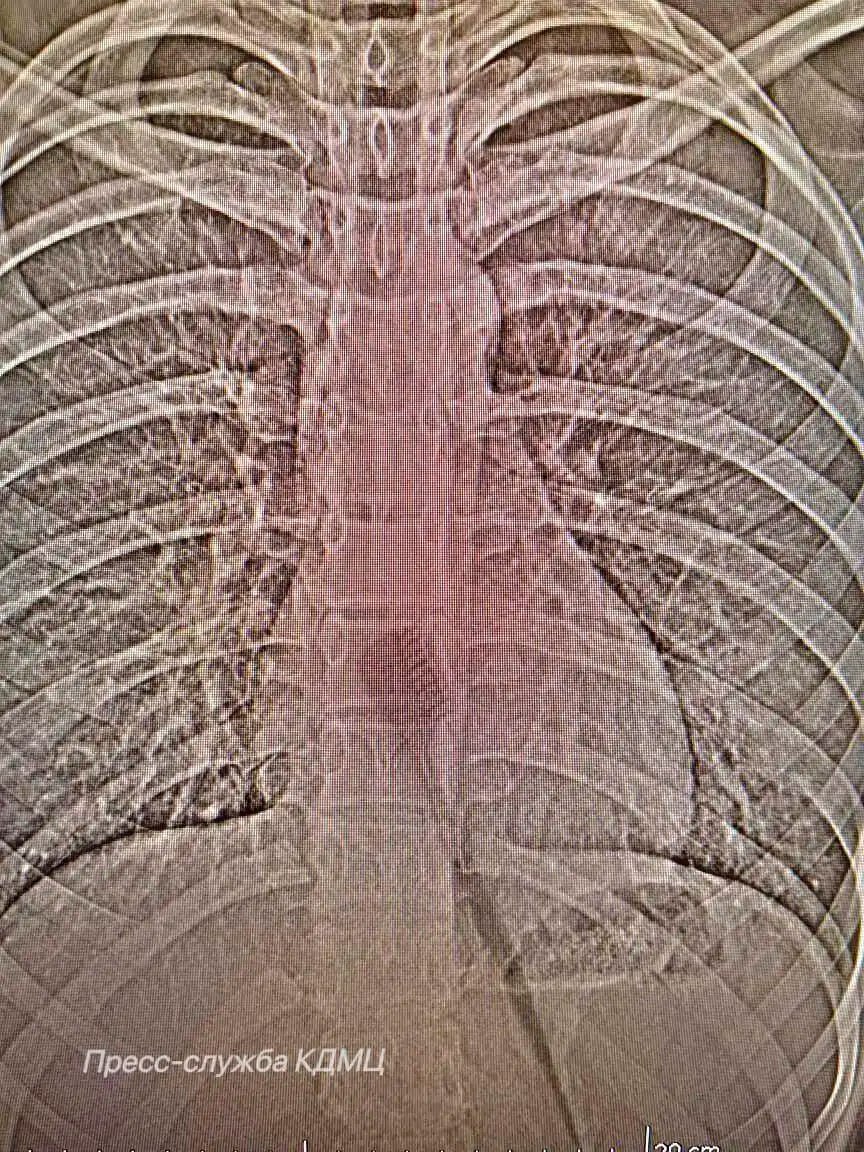

Девочке провели эндоскопическую операцию, которая позволила аккуратно удалить предмет через естественные пути, минимизировав риск осложнений и ускорив процесс восстановления.